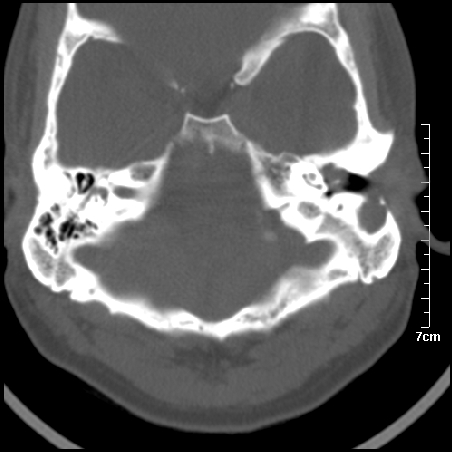

病例2

m/27

左侧板障型乳突。

左侧慢性中耳炎伴胆脂瘤形成。